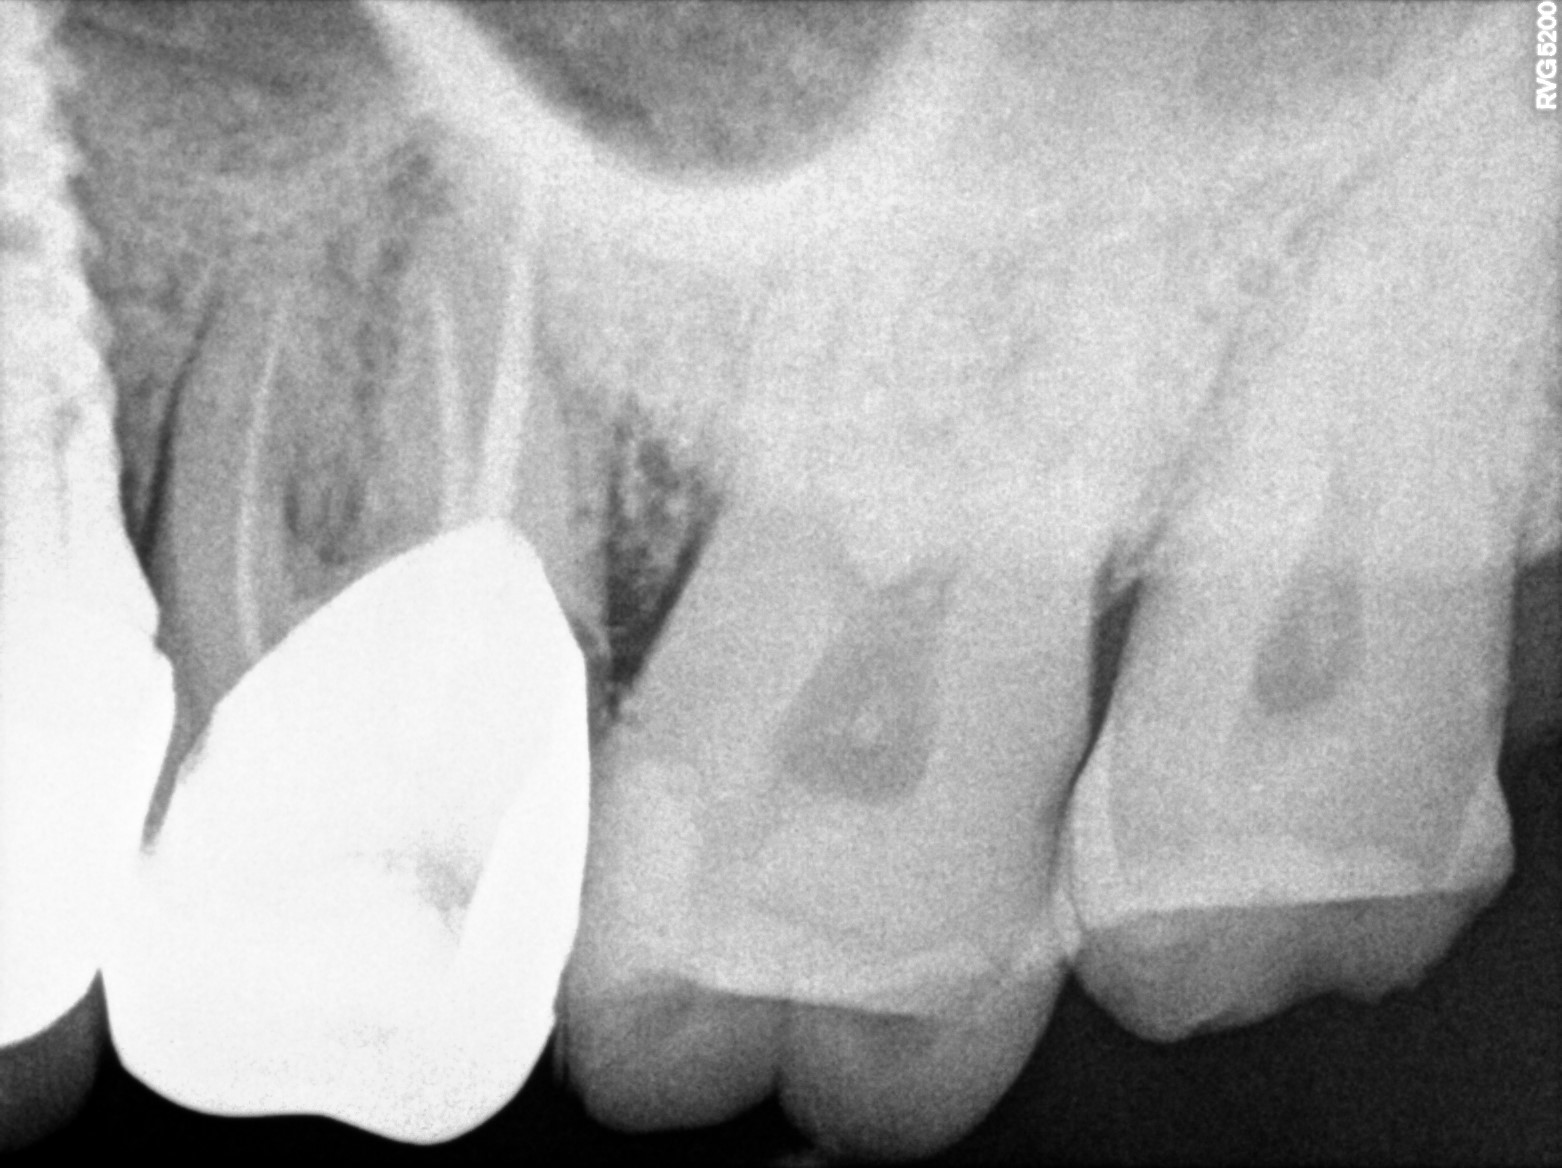

Dental Radiographs FHIR: DocumentReference · LOINC 24641-7

xray_1773475755_1.jpg

24641-7